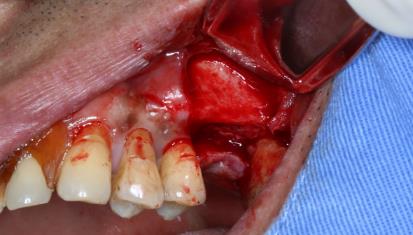

诊断:26牙缺失;  治疗:26牙行种植修复(经牙槽嵴上颌窦提升术)  治疗方式:术区行利多卡因+布比卡因阻滞麻醉,碧兰麻行浸润麻醉。常规消毒铺单,待麻药显效后,于26牙槽嵴顶做近远中切口,剥离术区黏骨膜,26远中做颊侧附加切口,显露术野。生理盐水冲洗冷却下大球钻修整骨面,小球钻确定26种植位点。先锋钻确定种植体植入方向,扩孔钻逐级扩大种植窝洞,窝洞预备至接近上颌窦底,插入深度测量尺观测深度与方向,扩孔钻扩大种植窝洞。使用上颌窦底冲压骨凿,轻敲骨凿底部至10mm,做鼻腔鼓气试验,检查上颌窦黏膜完整性,最终植入种植体,查种植体方向和初期稳定性良好,旋入覆盖螺丝。严密缝合创口。常规止血,术毕。

6个月后,行种植修复,安置修复基台,戴入固定修复体。